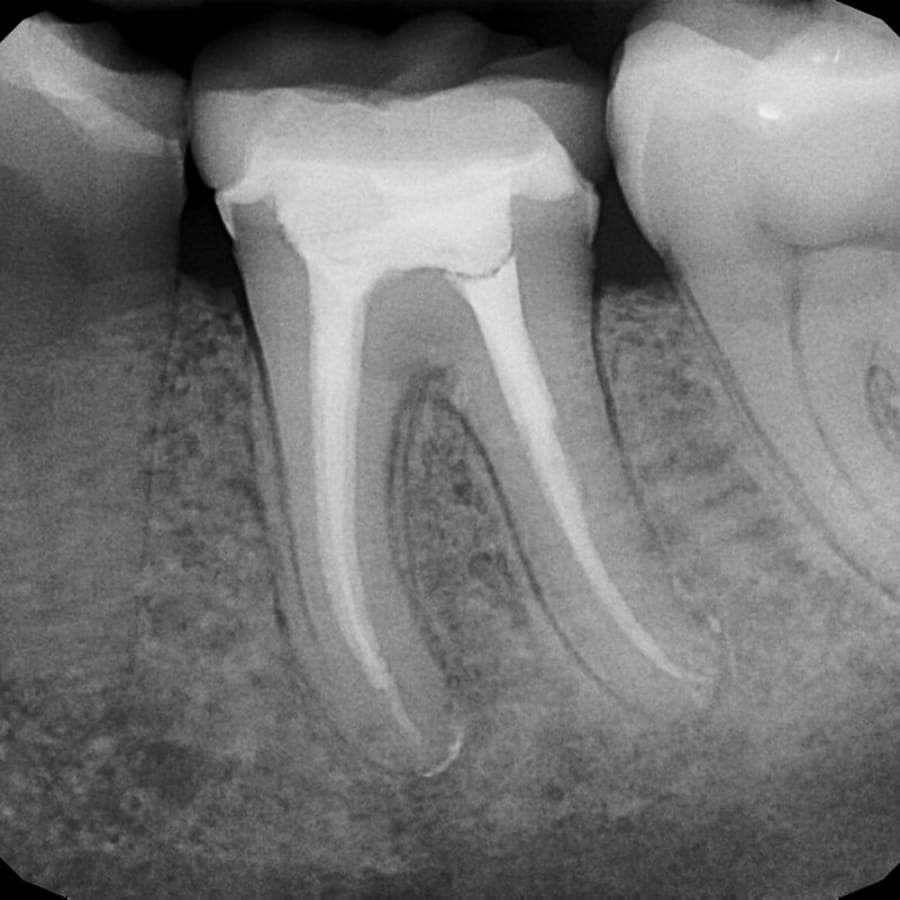

Tratamento de Canal

Terapia precisa e confortável para salvar o dente, com tecnologia rotatória que garante eficiência e rapidez.